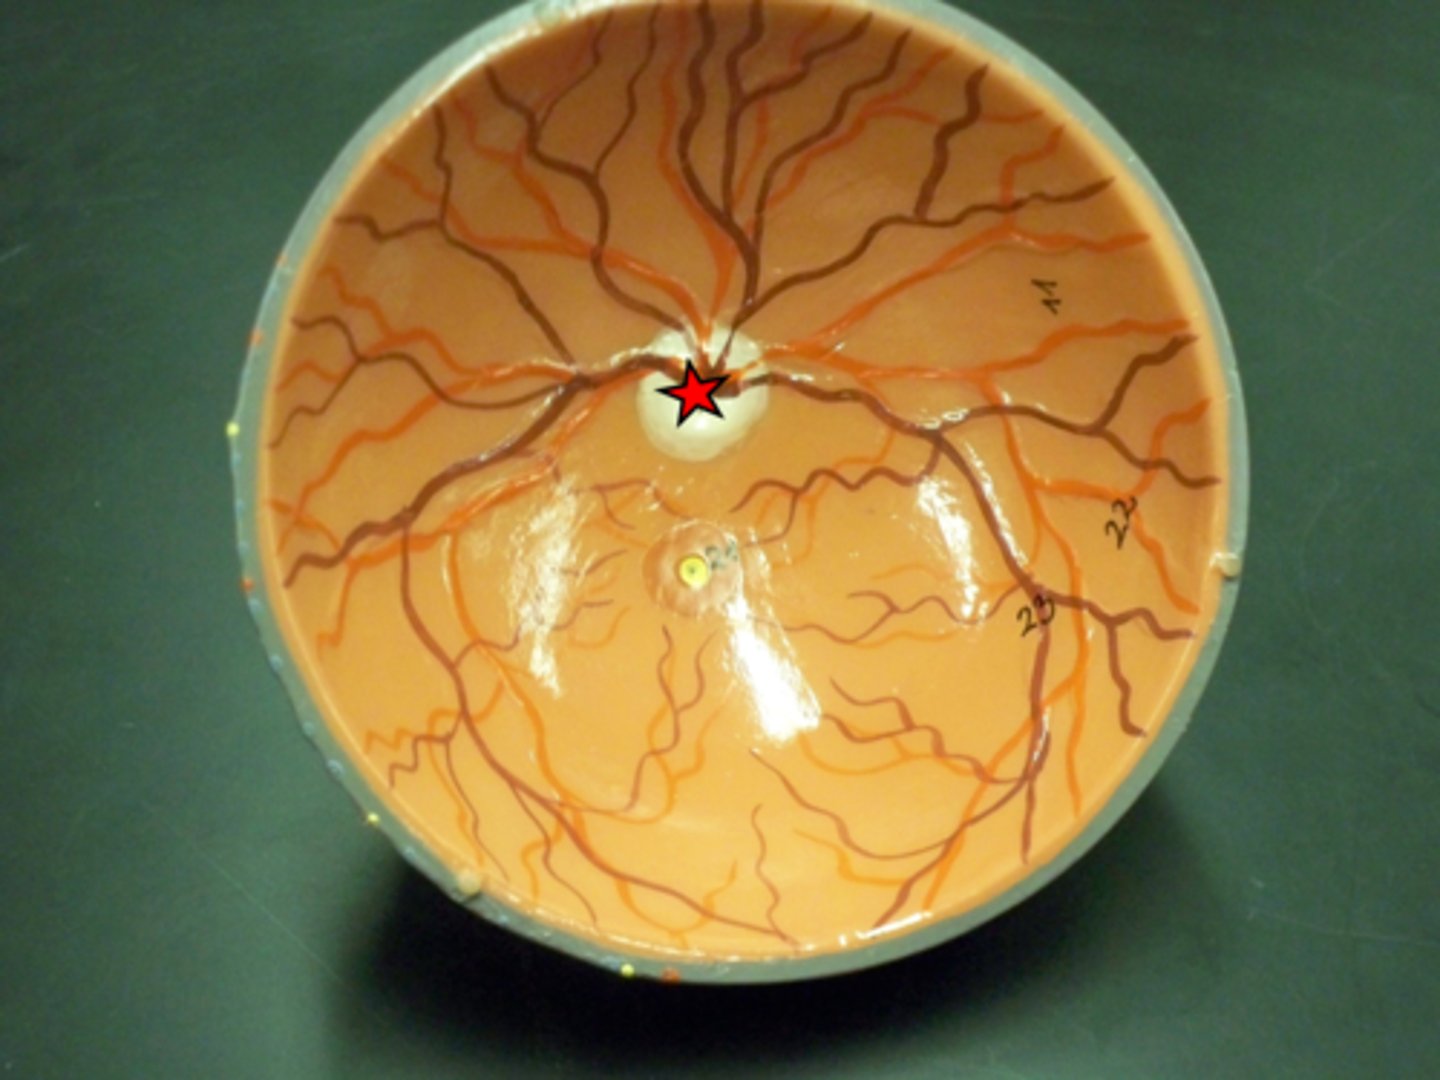

Pupil

Iris

Sclera

Cornea

Aqueous humor

Optic disc

Vitreous humor

lens

ciliary body

retina

layer being peeled off

choroid

fovea centralis